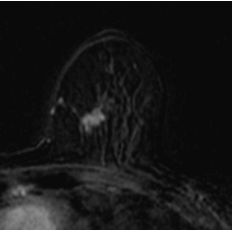

Review of the file in a specialized center before surgery showing multicentricity with additional distortion of the internal quadrants ACR5, noted by the Mammoscreen® analysis. The analysis revealed an MRI lesion assembly over 5 cm in height, 2.5 cm in transverse diameter, as well as a non-inflammatory global left breast retraction. The case results in a modification of the surgical pec initially planned with total mastectomy.

Case from the practice of Dr. Daroles